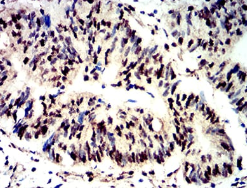

Phospho-4E-BP1 (Ser65)单克隆抗体[2D1G1]

Phospho-4E-BP1 (Ser65) Mouse Monoclonal antibody[2D1G1]

IHC    1/200 - 1/1000